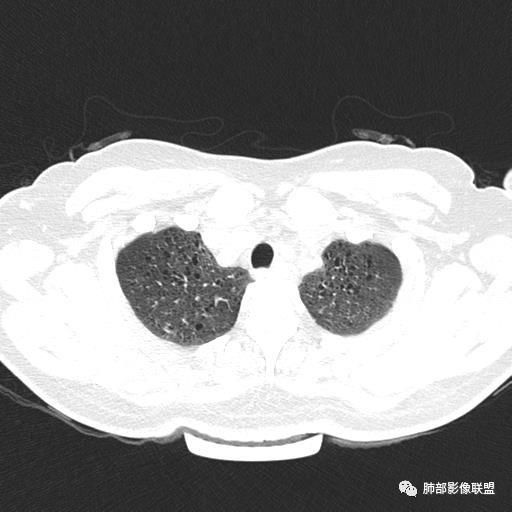

中年女性,不吸烟

双肺弥漫囊腔,累及肋膈角,囊腔形态相对规则单一。

符合LAM

CT平扫示双肺弥漫分布大小不等囊状薄壁透光区,无内、中、外带分布差异,间质稍示增厚。拟LAM

中年女性育龄期妇女,咳嗽气喘,无吸烟史,有苯吸入史。影像:双肺弥漫均匀小囊腔,无明显分布优势,囊腔形态欠规则,壁薄,部分囊腔边缘血管征,伴双肺弥漫磨玻璃影,无结节,考虑lam,鉴别苯中毒肺损伤,囊腔多有分布优势,小叶中心分布为主,形态规整等

女,46,活动性气喘1年。苯吸入史半年。胸部CT:两肺弥漫囊腔,上至肺尖,下至肋膈角,形态类似小囊腔。考虑:LAM,鉴别LIP,BHD,PLCH等。

双肺弥漫大小不一薄壁含气囊腔,囊间肺组织正常,正常肺背景,肺尖肺底受累;青年女性,气喘,支持LAM

双肺多发大小相近的囊状影,分布趋势趋于一致,中年女性,考虑LAM。部分囊内见血管及分隔影,小叶中心性肺气肿代排

CT表现:双肺弥漫大小不等的薄壁囊腔,囊壁<2mm,外形规则,血管影多位于囊腔周围,囊腔之间肺组织正常,随着疾病进展到晚期,囊腔变大、增多,不可胜数,囊腔可融合成较大的囊,与肺气肿相似,形成间质性肺纤维化。部分病例可出现结节影。